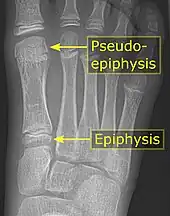

Pseudo-epiphysis

A pseudo-epiphysis is an epiphysis-looking end of a bone where an epiphysis is not normally located.[6] A pseudo-epiphysis is delineated by a transverse notch, looking similar to a growth plate.[6] However, these transverse notches lack the typical cell columns found in normal growth plates, and do not contribute significantly to longitudinal bone growth.[7] Pseudo-epiphyses are found at the distal end of the first metacarpal bone in 80% of the normal population, and at the proximal end of the second metacarpal in 60%.[6]